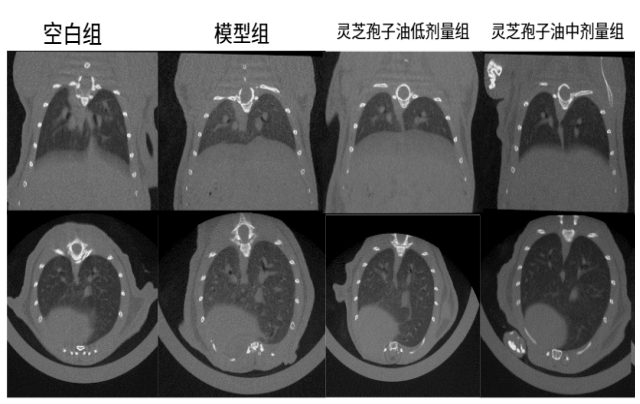

體內(nèi)功效實(shí)驗(yàn)研究結(jié)果表明:在為期52天的小鼠實(shí)驗(yàn)中,每日6粒廣藥牌靈芝孢子油,靈芝孢子油顯著減少了肺部肉芽腫結(jié)節(jié)的面積(減少23.07%)和磨玻璃陰影,降低炎癥因子和趨化因子水平 ,證實(shí)廣藥牌靈芝孢子油具有一定的防治小鼠肉芽腫型肺結(jié)節(jié)的作用。

圖:靈芝孢子油對肉芽腫型肺結(jié)節(jié)小鼠肺部斷層掃描檢測結(jié)果及統(tǒng)計